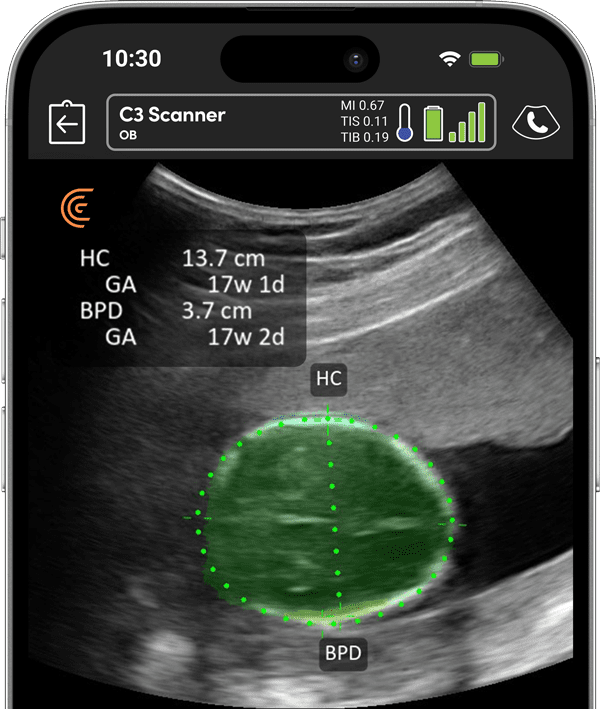

双頭骨径(BPD)、頭囲(HC)、腹囲(AC)、大腿骨長(FL)は、妊娠第2期と第3期に妊娠月齢と体重を推定するために行われる測定です。クラリアスC3スキャナーは胎児の解剖学的構造の優れた解像度を提供し、測定をより正確にします。